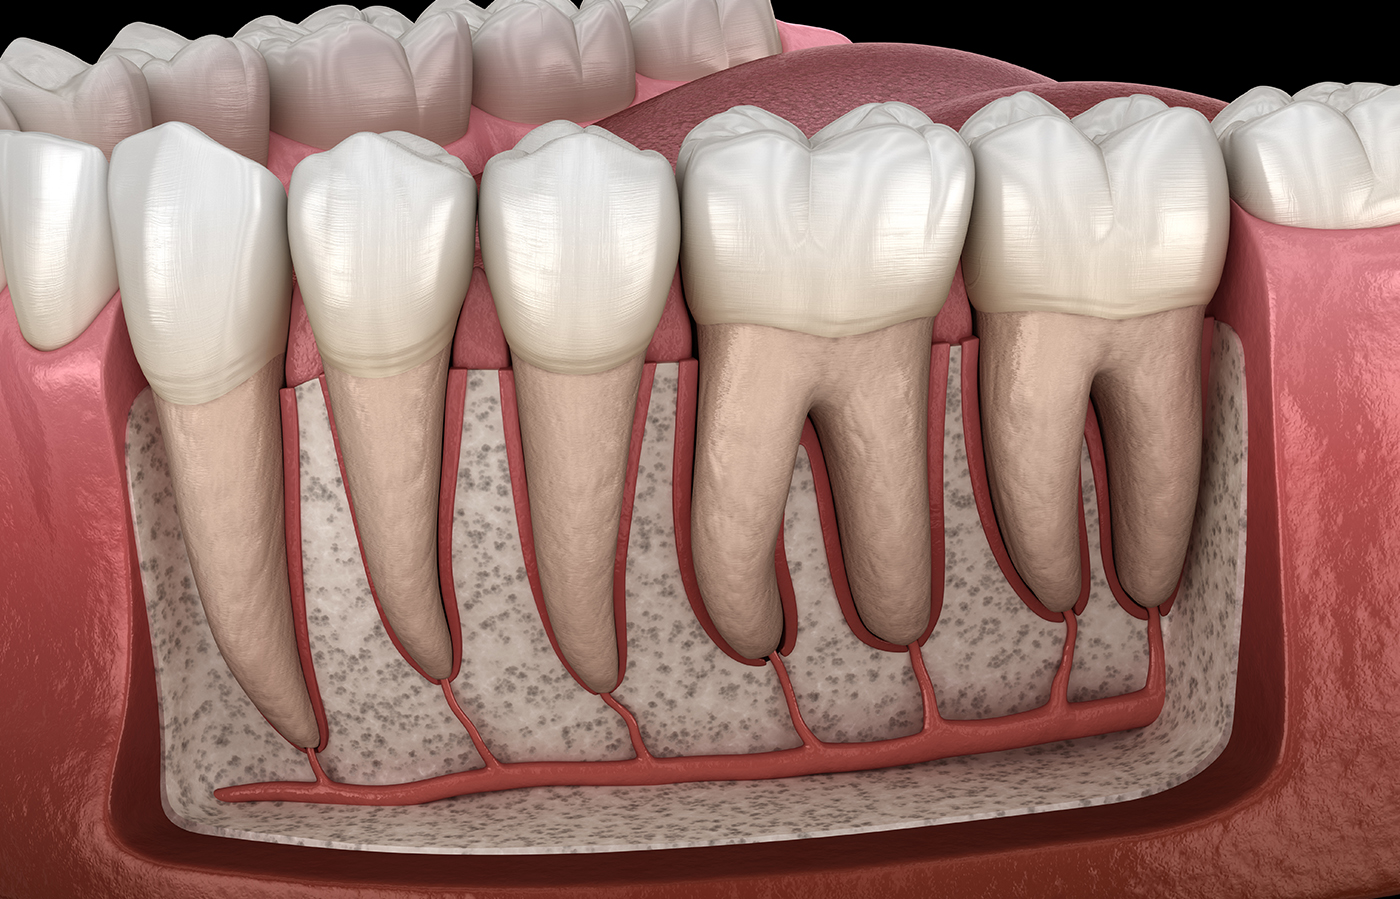

通院回数が多い理由は、歯の根の中にある管は、複雑な構造を持っているため、むし歯に感染した部分をしっかり取り除くまで時間がかかるからです。

通院回数が多い理由は、歯の根の中にある管は、複雑な構造を持っているため、むし歯に感染した部分をしっかり取り除くまで時間がかかるからです。

根管は歯によって形状が異なり、非常に複雑な構造をしているため、通院回数が他の治療に比べて多い傾向があります。通常7〜8回程度を目安に治療を行いますが、患者さんの症状やお口の状態に応じて異なる場合があります。

歯の内部の血管や神経を取り除き、「根管長測定器」を使用して根管の長さを測定します。

根管の清掃

むし歯菌に感染した歯の内部の歯質を徹底的に取り除きます。